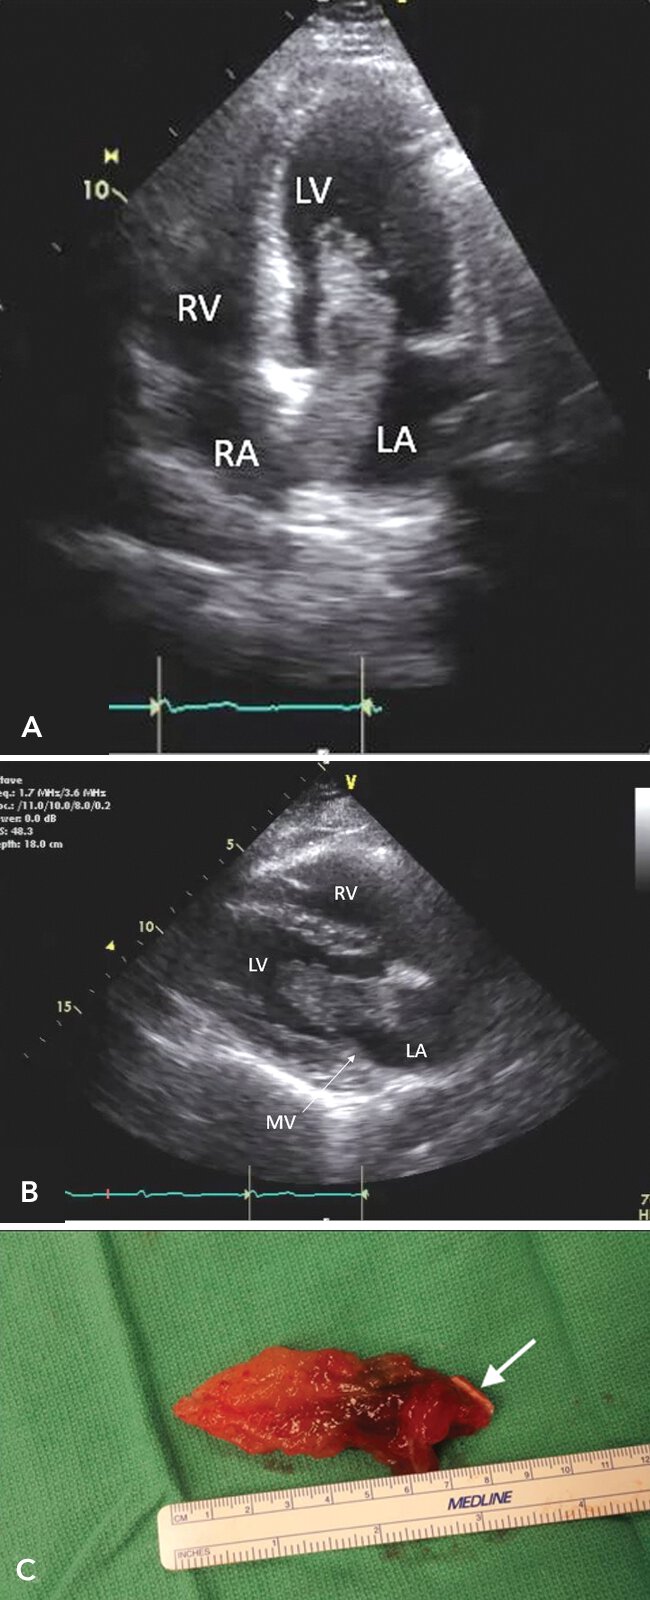

500

Atrial myxoma.